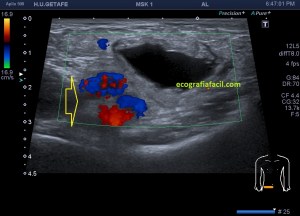

En el caso que te traigo hoy no hizo falta buscar mucho, nada más poner la zona en corte transverso en la región inguinal derecha, cerca de los labios mayores, la paciente tenía una masa blanda, ligeramente dolorosa durante la exploración que había aumentado ligeramente tiempo atrás y que ecográficamente tenía un aspecto anecoico,imagen 1, de paredes finas, más grande en su eje lateral que en el eje antero posterior y que se deformaba con la ligera presión del transductor y que no modificaba su ecoestructura con la maniobra de Valsalva.

En cuanto localicé este hallazgo realicé corte transverso (imagen 2) y longitudinal (imagen 1), con medidas y estudio en modo doppler para ver vascularización (imagen 3, flecha amarilla), seguidamente, era muy importante asegurar algunas referencias locoregionales como los grandes vasos femorales, siempre debemos documentar esta coexistencia y buscar un cuello que puedes observar con las dos flechas rojas de la imagen 1 y que la ecoestructura marca perfectamente al ser anecoica.

Aunque no muchas, ya había visto alguna vez esta entidad y sabía que era un Quiste de Nuck, pero necesitaba buscar los hallazgos anatómico ecográficos previamente comentados, como la localización junto a los grandes vasos y el cuello, para poder presentarlo a la radióloga para que realizase el informe, que corroboró lo que pensaba, lo cual no tiene relevancia alguna. Esta patología puede ser conocida también como Hidrocele de Nuck.

1

2

3